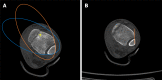

Case summary: A 16-year-old patient sustained left medial malleolar fracture, and the associated inferior tibiofibular syndesmotic instability was overlooked. After open reduction and internal fixation of the medial malleolar fracture, inferior tibiofibular syndesmosis diastasis with IOM rupture was detected by auxiliary imaging. Secondary surgical intervention was performed to reduce anatomically and fix with two trans-syndesmosis screws. Twelve weeks later, the screws were removed. At the 6-mo follow-up, the patient gained full range of motion of the ankle.